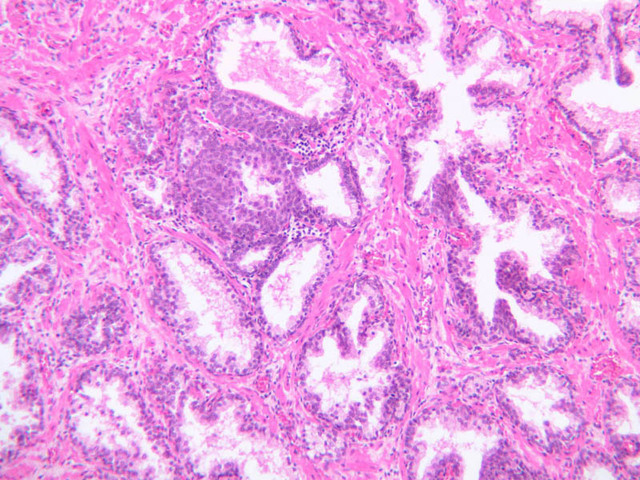

The prostate is an aggregate of numerous tubulo-alveolar glands embedded in a dense stroma of collagen fibers and smooth muscle (B-90 [2.5x, 10x, 20x, 40x-labeled]; B-91 [2.5x, 10x, [[http://www.medicalhistology.us/wiki/bin/viewfile/Main/ProstateImages?rev=1;filename=b91_prostate_adult_20x_he.jpg[20x]], 40x-labeled] [2.5x, 10x, 10x, 20x, 40x]). Note that the prostatic urethra, the portion of the urethra which runs through the prostate gland, is also present (B-91 [2.5x, 10x, 20x, 40x]). Under high dry magnification, it is obvious that the glandular epithelium varies from simple cuboidal to pseudostratified columnar. Prostatic acini often contain eosinophilic corpora amalacea (prostatic concretions) (B-90 [2.5x, 10x, 20x, 40x-labeled]). The number and degree of calcification of these spherical, lamellated structures increase with age. In some sections, the prostatic urethra can be identified. Functional, as well as morphological, maintenance of the adult prostate and seminal vesicles depends on adequate levels of circulating testosterone. Examine the prepubertal prostate (B-92 [2.5x, 10x, 20x, 40x] [2.5x-labeled, 10x, 20x, 40x]). How does this specimen differ from that on slide B-90?